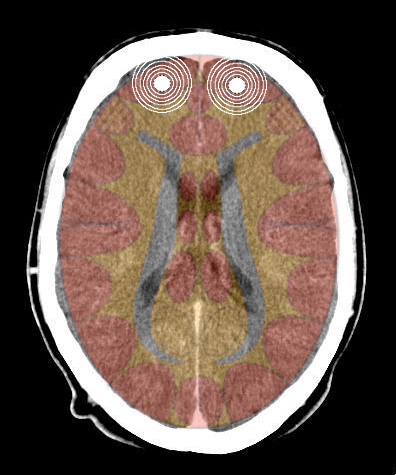

La Corteccia territoriale si colloca nel lobo dell'insula, che si trova in una cripta corticale, come vedete dall'immagine qui sotto.

Si attiva in caso di:

- Attivazioni sessuali (frustrazione sessuale, sentito femminile di "non essere presa") legati a vene coronarie, collo dell'utero e vescicole seminali.

- Attivazioni di identità (non sapere dove collocarsi, il proprio ruolo nel gruppo) legati alla mucosa rettale.

- Attivazioni territoriali:

- minaccia nel territorio (mucosa bronchiale);

- spavento inaspettato (laringe);

- perdita di territorio (arterie coronarie);

- ingiustizia, rancore nel territorio (piccola curvatura dello stomaco e del duodeno, vie biliari e pancreatiche);

- non poter marcare o delimitare il proprio territorio (maschile) e non poter riconoscere i límiti del proprio territorio (femminile) legati a mucosa della vescica, emiparti destra e sinistra.

- Insula destra = ormonalità, percettività e comportamento maschile, sia nella femmina che nel maschio, destrimane o mancino. Quando attivata causa tonalità depressiva;

- Insula sinistra = ormonalità, percettività e comportamento femminile, sia nella femmina che nel maschio, destrimane o mancino. Quando attivata causa tonalità maniacale.